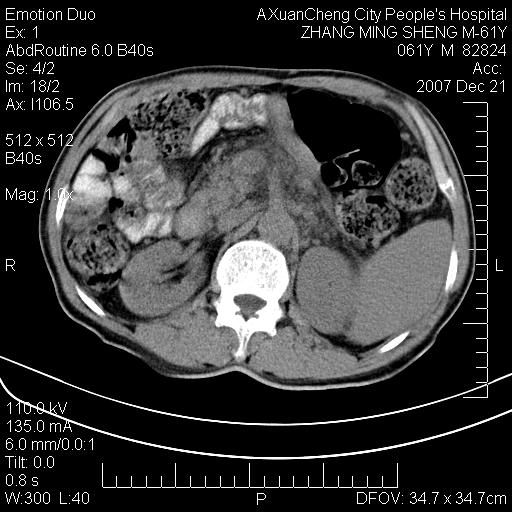

标题: CT11031:M61Y,胰腺占位 [打印本页]

标题: CT11031:M61Y,胰腺占位

大家侃侃门静脉和胆管系统怎么回事,肝内转移?

胰腺癌肝转移

肝硬化,门脉高压,脾肿大;弥漫性肝癌,肝内、门脉、腹膜后淋巴结转移,肝内外胆管扩张,胰头区占位,建议mr检查

胰腺癌伴肝内转移;门脉、肠系膜上v癌栓形成。

考虑为:胰腺癌伴肝脏转移、腹膜后淋巴结转移,门静脉及肠系膜上静脉瘤栓形成。

胰体尾癌伴肝内转移,门静脉及肠系膜上静脉瘤栓形成.